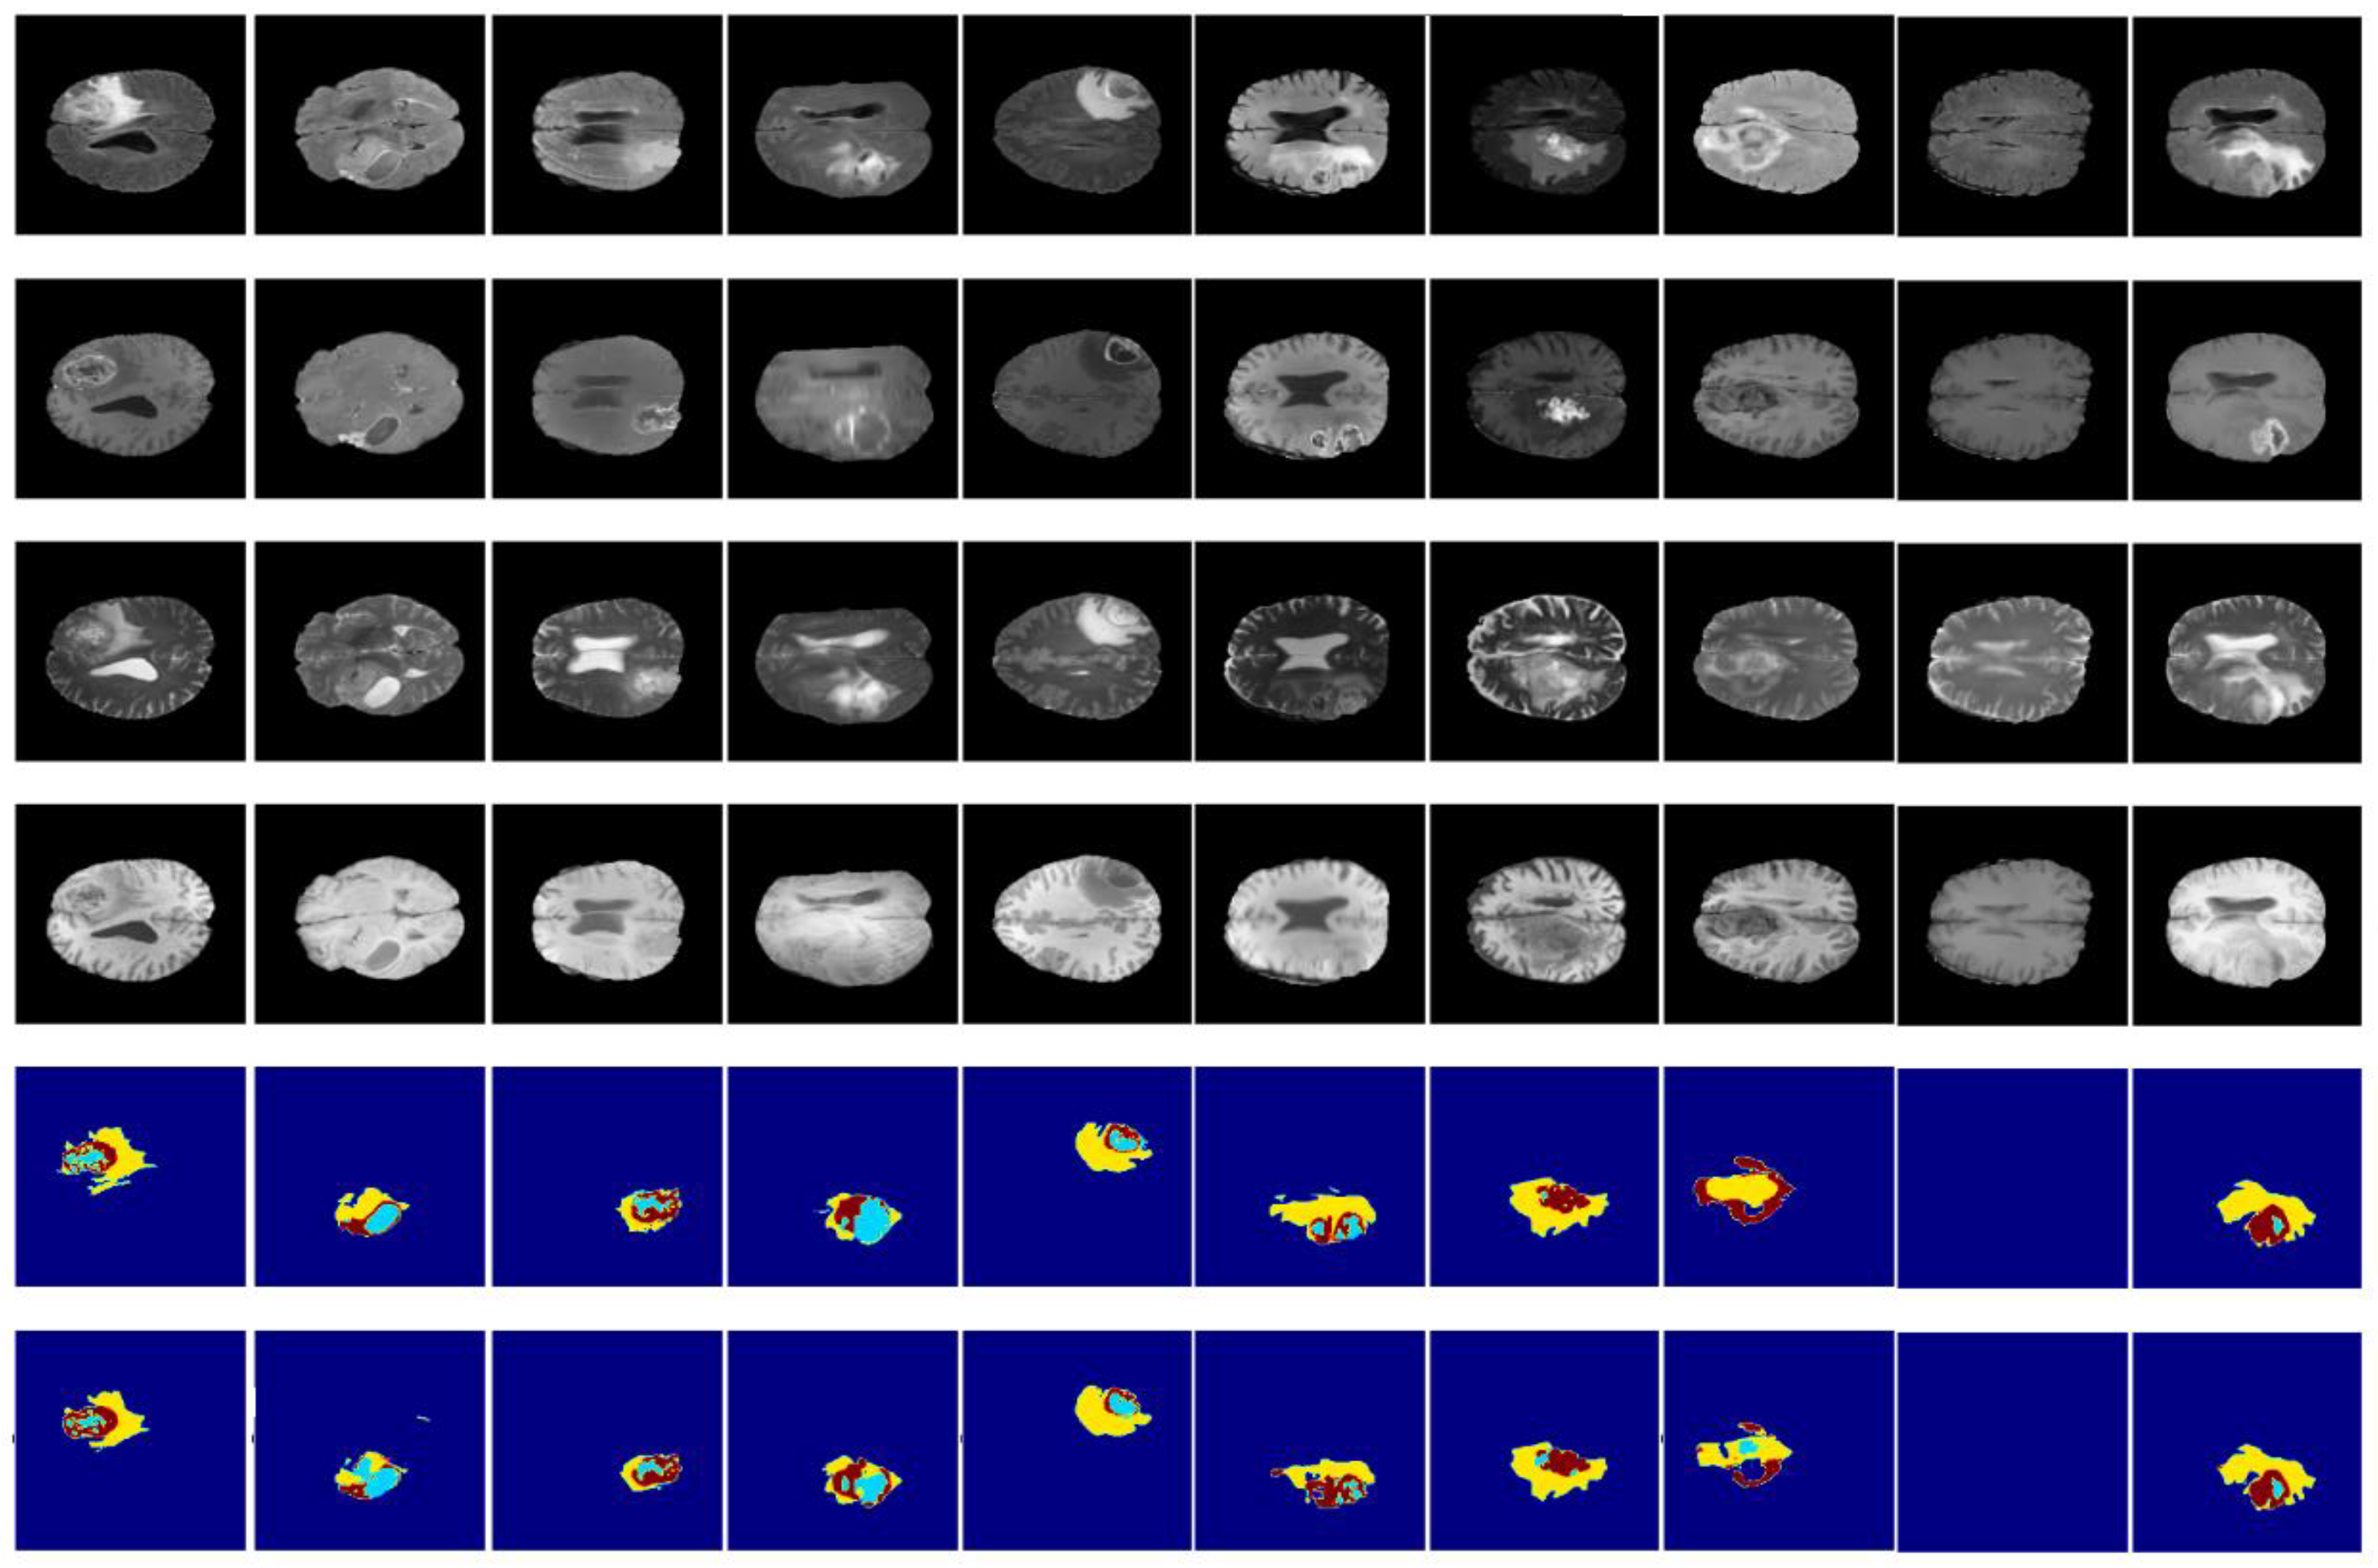

2. Materials and Method

2.1. Data and Data Preparation

2.1.1. Dataset

2.1.2. Data Preparation

3.3. Results and Discussion